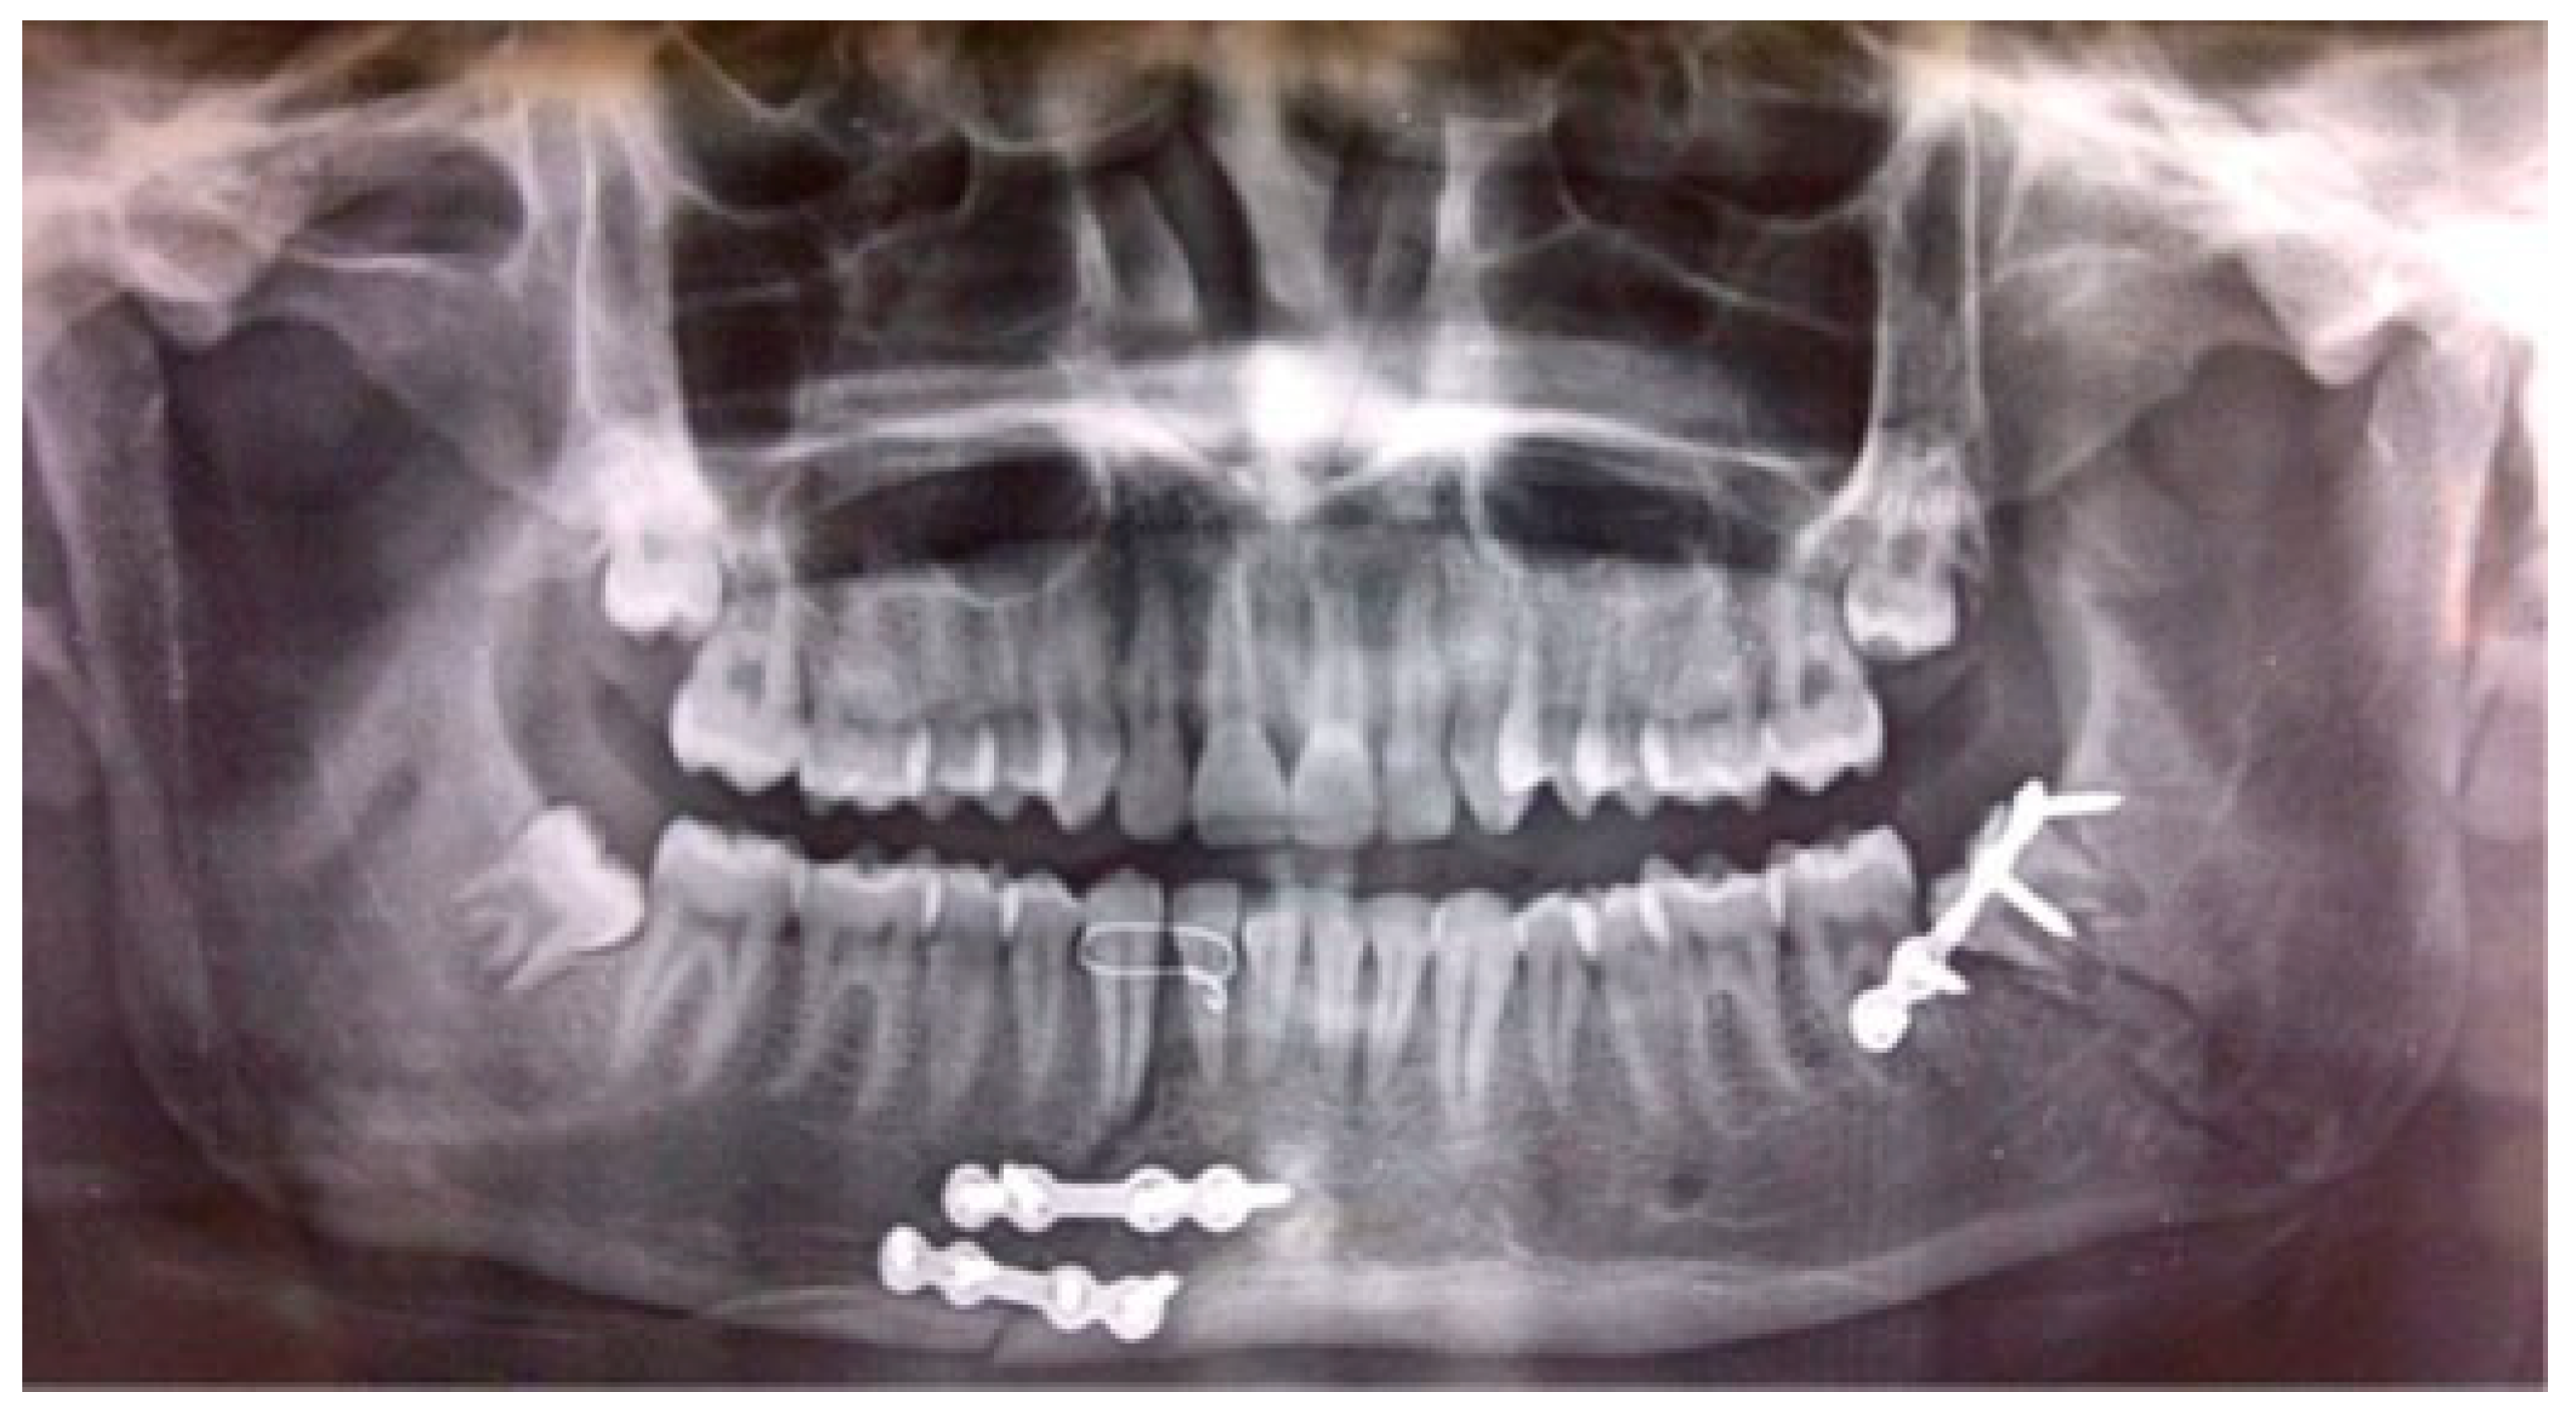

Figure 5. Postoperative orthopantomography reveals the adequate reduction and internal fixation of fractured segments following placement of embrasure wires.